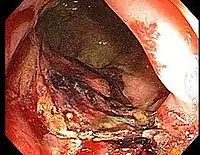

Chronic radiation proctitis

• Timing: 9-14 months after RT, but sometimes after 2 years (and as late as 30 years)

• Etiology: obliterative endarteritis and chronic mucosal ischemia, leading to progressive epithelial atrophy and fibrosis. Ultimately, development of a chronically ischemic intestine prone to fibrosis and bleeding

• Symptoms: diarrhea, obstructed defecation (if strictures), bleeding, rectal pain, rectal urgency, and fecal incontinence. Rarely fistulas, SBO

• Diagnosis: colonoscopy, barium studies if suspecting strictures and fistulas